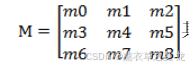

在传统的中值滤波方法中,就是直接对w0~w8。进行排序,然后取中间的值作为该像素的灰度值.这样边缘信息就会被削弱。为了增强边缘信息。针对矩阵构造一个中间矩阵M:

其中 mi为无符号数,并设定一个边缘附近的灰度阈值为f,则令mi=f,i∈[0,2]的整数;mi=wi,i∈[3,8]的整数。然后按传统的中值滤波法对矩阵M进行排序,选取中间值。

因为在轮廓的边缘处,m3~m8中,必定既有大于f的值,也有小于f的值,排序结果顺序会满足背景像素、f、前景像素这样的次序,所以这样就会使得排序结果的中间值一定为m0~m2中的一个,即为r,边缘处的像素就设定为了返回像素的灰度值,从而突出了边缘信息;在其它地方,m3~m8中除孤立噪声像素外,要么同大于f要么同小于f,所以m0-m2对排序结果影响不大,能去除孤立噪声。